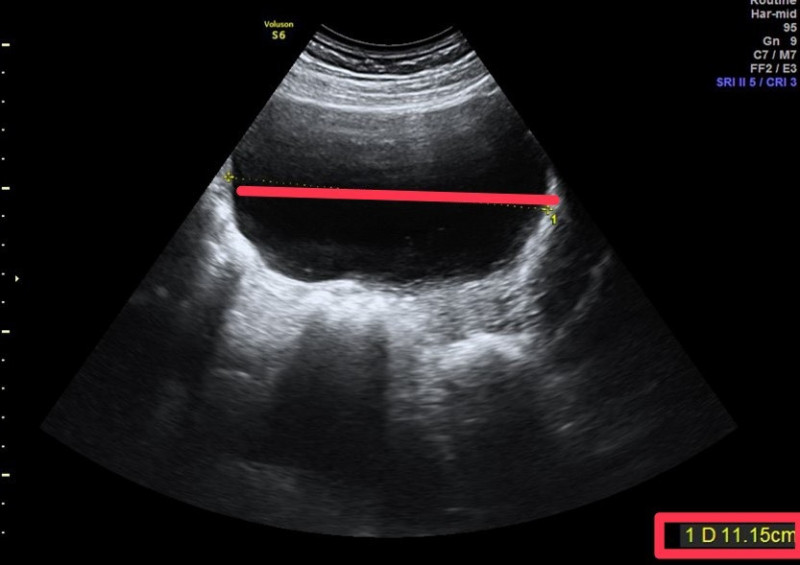

林新旺指出,患者旅日前就醫婦產科門診,健檢發現左側卵巢囊腫,從超音波影像明顯可見,左側卵巢有顆11 X 10公分的巨大卵巢囊腫,由於囊腫過大,建議以腹腔鏡摘除囊腫,約定在旅日後手術。